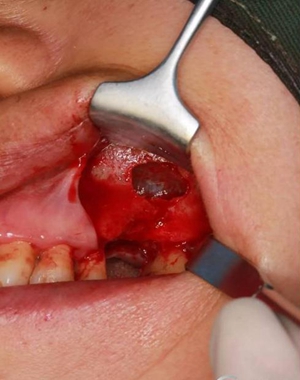

改良式外提升工具盒-外提 科貿(mào)嘉友收錄

大家好,我是梁老師的助理小依。由于梁老師每天手術(shù)檔期安排較滿,加上經(jīng)常出差講課,沒有時(shí)間整理病例 。為了方便大家更及時(shí)的了解梁老師最新手術(shù)動(dòng)態(tài),以后將由我為大家整理并推送梁老師最新經(jīng)典案例。案例文字旁白少,但圖片會(huì)盡量完整展示手術(shù)全過程,供大家學(xué)習(xí)參考。有任何問題,可以留言,梁老師會(huì)親自為大家解答。感謝大家對梁老師的支持和關(guān)注!